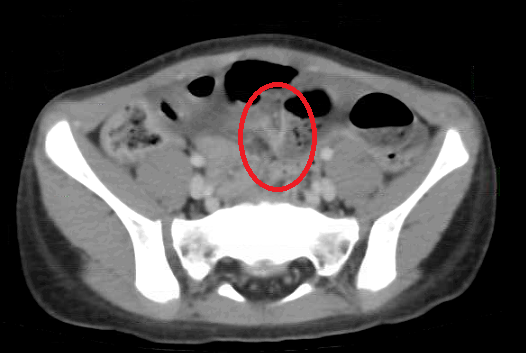

Hình 2: hình ảnh nghi tắc ruột do dây chằng trên

phim chụp Cắt lớp vi tính

thuật nội soi cắt ruột thừa cách đây 3 tháng. Sau khi được làm các xét nghiệm chẩn đoán tắc

ruột, BN cũng đã được phẫu thuật để giải